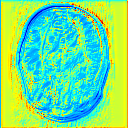

Reconstructing magnetic resonance (MR) images from undersampled data is a challenging problem due to various artifacts introduced by the under-sampling operation. Recent deep learning-based methods for MR image reconstruction usually leverage a generic auto-encoder architecture which captures low-level features at the initial layers and high?level features at the deeper layers. Such networks focus much on global features which may not be optimal to reconstruct the fully-sampled image. In this paper, we propose an Over-and-Under Complete Convolu?tional Recurrent Neural Network (OUCR), which consists of an overcomplete and an undercomplete Convolutional Recurrent Neural Network(CRNN). The overcomplete branch gives special attention in learning local structures by restraining the receptive field of the network. Combining it with the undercomplete branch leads to a network which focuses more on low-level features without losing out on the global structures. Extensive experiments on two datasets demonstrate that the proposed method achieves significant improvements over the compressed sensing and popular deep learning-based methods with less number of trainable parameters. Our code is available at https://github.com/guopengf/OUCR.